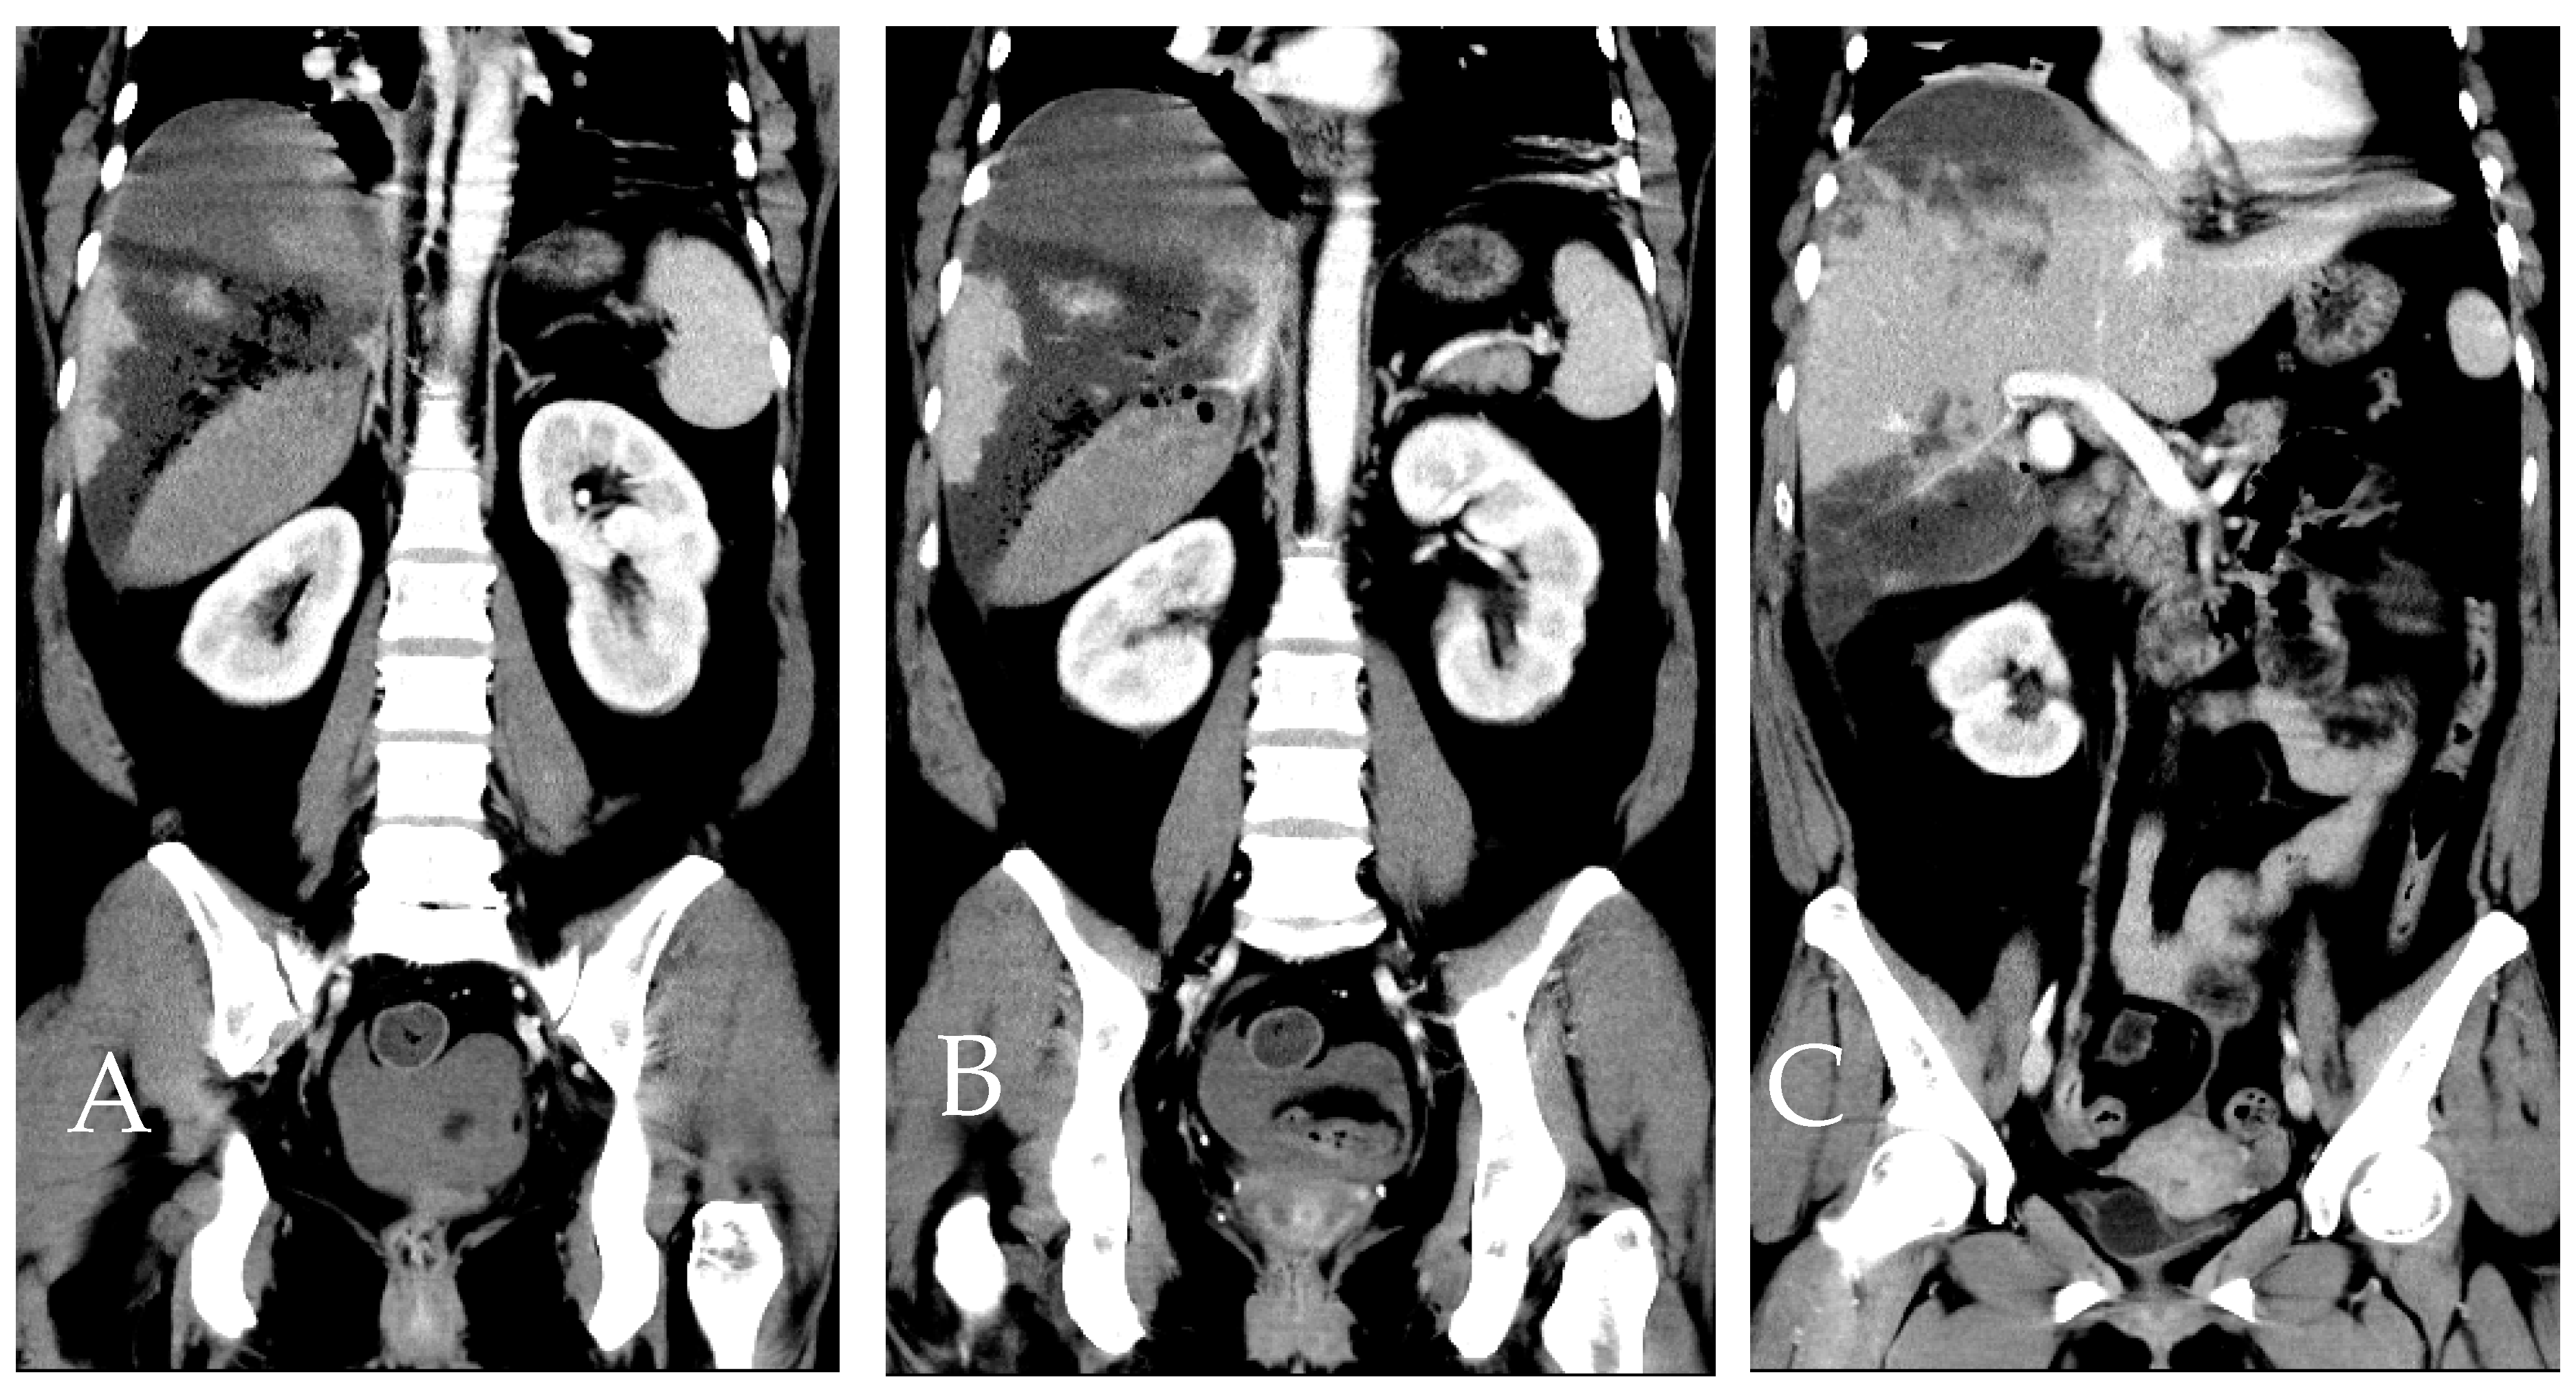

Figure 9. Dynamic CT scan in the artery phase, presented as a coronal view reconstruction. (AC) Sections from ventral side (A) to caudal side (C) illustrate various planes of the patient. When correlated with the axial view from Figure 8, the approximate location of necrosis can be pinpointed to segments 6 (S6) and 7 (S7) of the liver that was not related to our embolization [2].